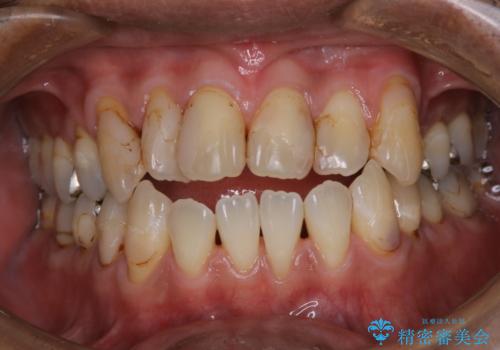

マウスピースをしたままコーヒーを飲むと着色がすごい

インビザライン中とインビザライン後のbefore、afterのクリーニング